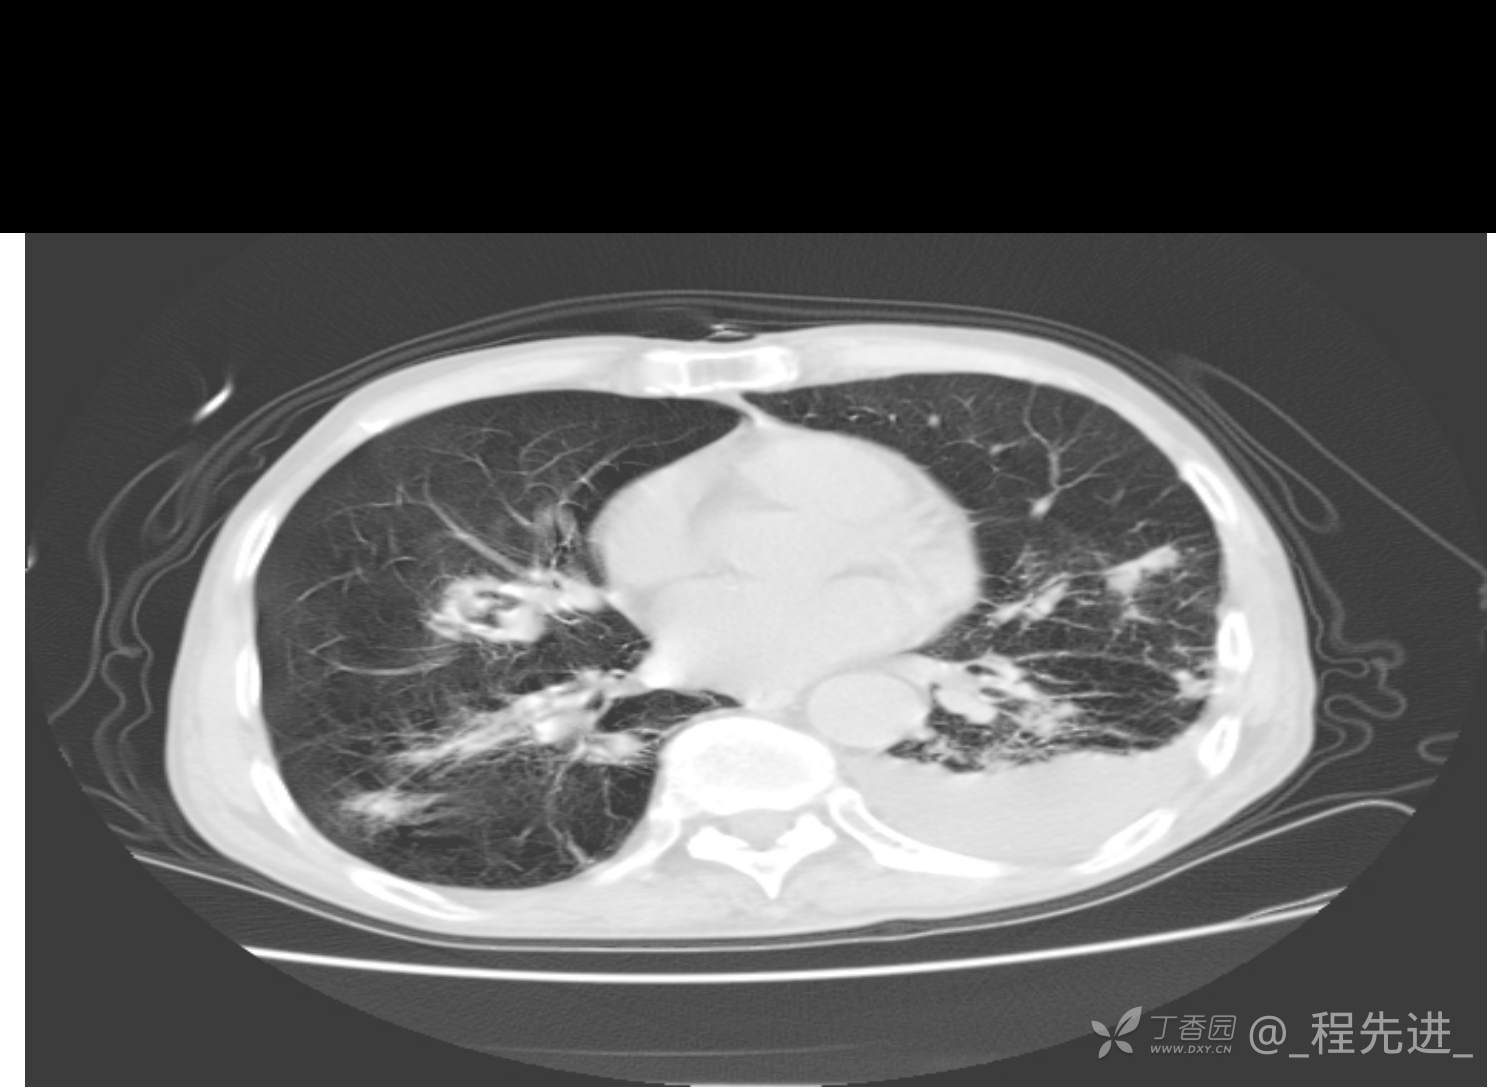

患者性别:男

患者年龄:81岁

简要病史:反复咳嗽、咳痰20余年,加重1周。两肺呼吸音低,可闻及散在干湿啰音。